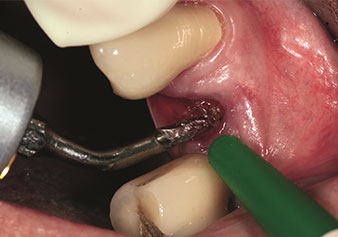

Indikation Alveolenmanagement

Eine oft unterschätzte Anwendung ist die schonende Extraktion von Zahnwurzeln oder auch von Wurzelfragmenten im Rahmen des Alveolenmanagements. Mit den feinen Periotomen, die aktuell in zwei Ausführungen (EX1 und EX2 von W&H) zur Verfügung stehen, lassen sich auch speziell endodontologisch vorbehandelte Zähne oder ankylosierte Wurzeln mühelos entfernen. Das Ergebnis sind Extraktionsalveolen, deren Hart- und Weichgewebe völlig intakt sind, da in der Regel auf ein Aufklappen verzichtet werden kann.

Dies stellt anschließend eine optimale Basis für eine spätere oder Sofortversorgung mit Implantaten dar (Abbildung eins und zwei mit freundlicher Genehmigung von Dr. Torsten Conrad, Bingen a. Rhein).

Feines Periotome (Instrument EX1)

Abb. 1: Feines Periotome (Instrument EX1).

Foto: © Dr Torsten Conrad (Bingen a. Rhein)